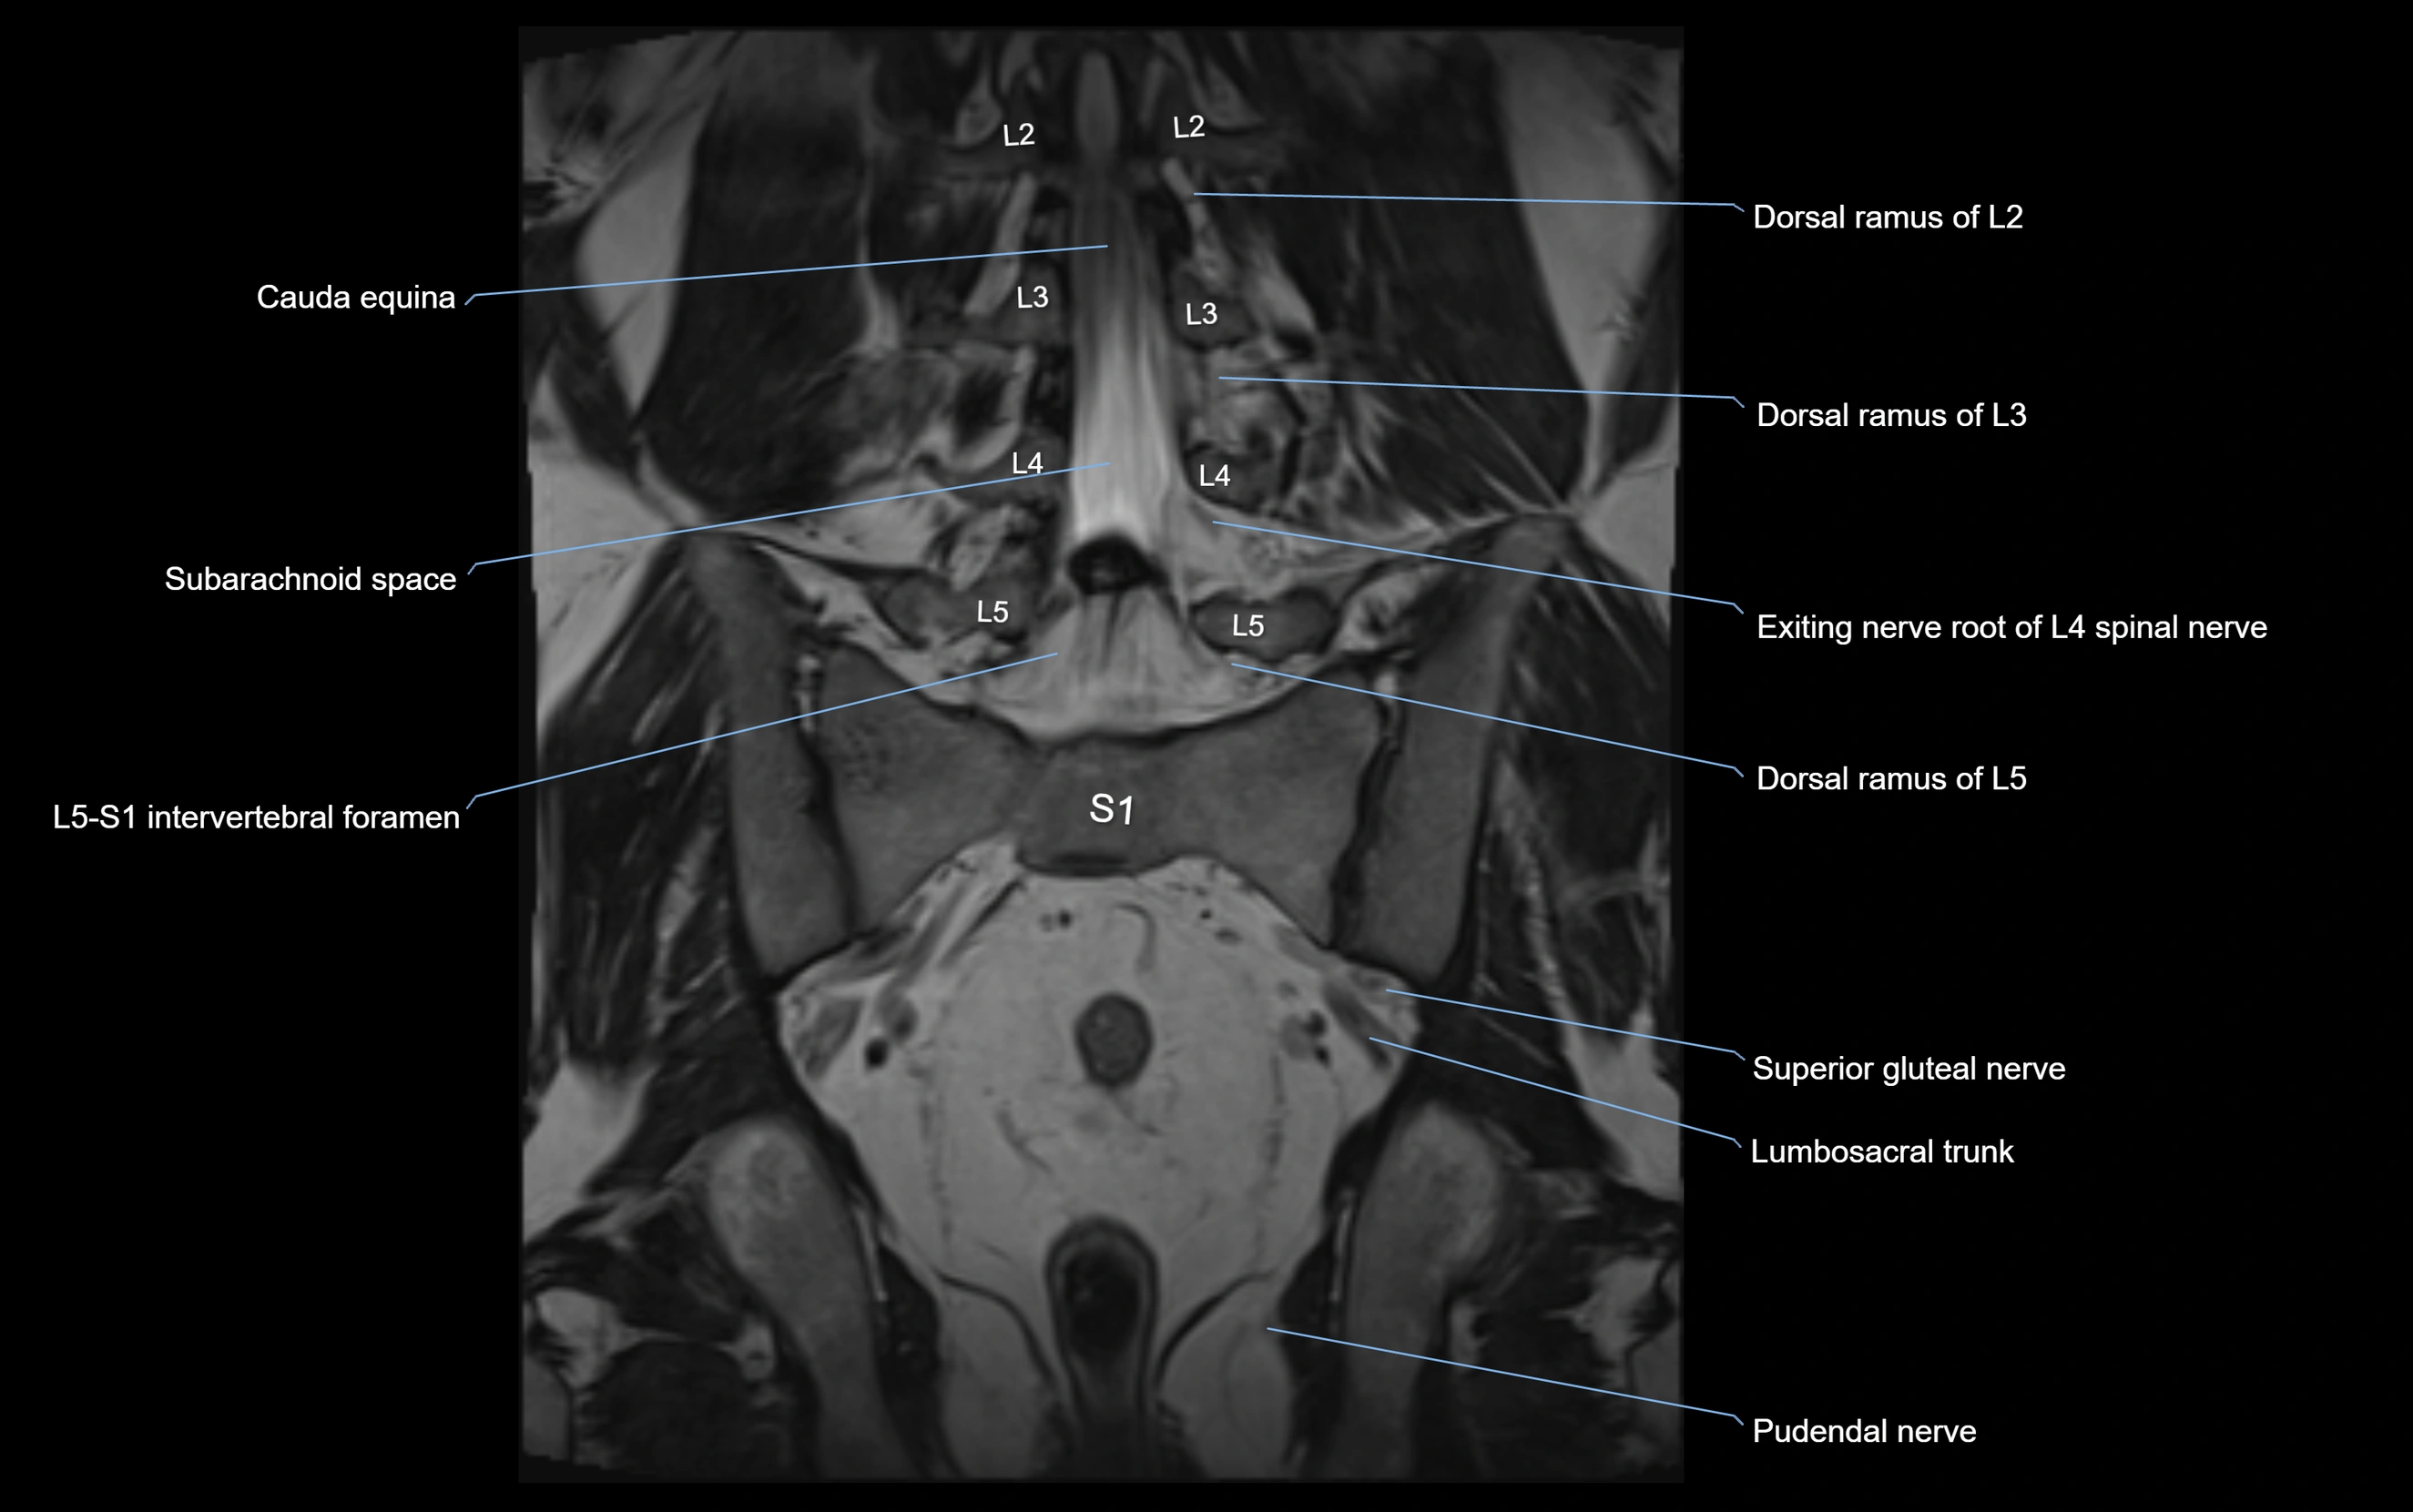

MRI image

image